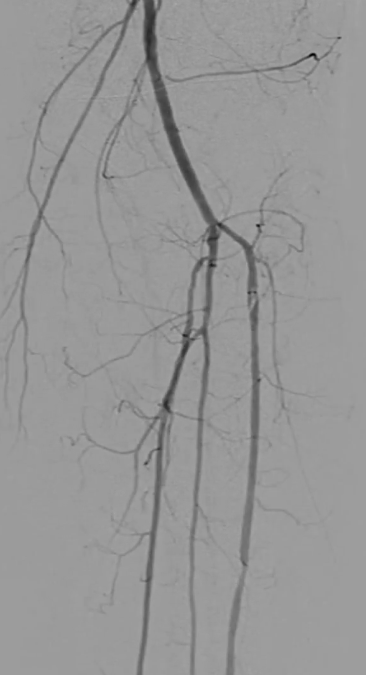

穿刺右侧股总动脉,置入8F翻山鞘,行左下肢动脉造影,可见左股浅动脉长段闭塞,远端流出道尚通畅。

既往支架已遮盖股浅动脉起始段